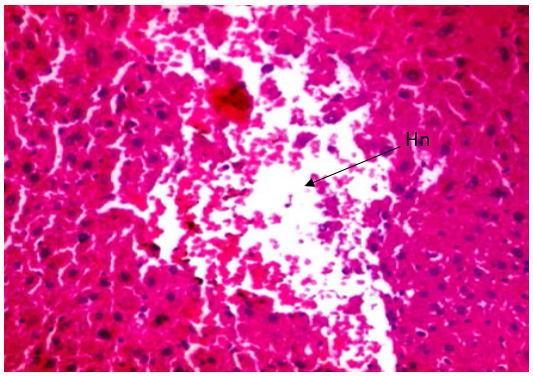

Figure 8.1a is a histological finding of the liver in Group 5 (GSK ‘SDG’) showing marked focal Hepatocytes Necrosis (Hn), hepatocyte drop-off and marked inflammations in adult male Wister Albino Rat treated with 0.31mls of alcohol for 30days as indicated using x 400 magnification while.

Histopathological profile of our research also provided empirical evidence for biochemical analysis. Examination of liver sections of rats revealed distortion of the normal structural organization of the hepatic lobules, and loss of characteristic cord-like arrangement of the normal liver cells, especially Figures 7.1a and 8.1a. This was seen with increase in the duration of exposure of the rats to the GSK. Several Liver cells were damaged and lost their characteristic appearance while others showed marked cytoplasmic vacuolization. The architecture of the liver elicited severe hepatic injury as evident by the observation of pathological changes in the architecture of the liver through focal necrosis, and degenerative changes in the hepatocytes. These pathological changes correlated well with the altered enzyme activities as reported in our early work [24]. This finding is also in agreement with the observations noted by the work of Gani and John, [25,26]. In their study, a significant increase in the activities of serum enzymes within 18 hours of exposure of the rats to single dose of D-Galactosamine Lipopolysaccharide (D-Gal N/LPs) induced hepatotoxicity in rats indicating the severity of hepatocellular injury. Rats given D-Gal N/LPs elicited severe hepatic injury as confirmed by the observation of pathological changes like infiltration of inflammatory cells, Kupffer cell hyperplasia, neutrophil accumulation and focal necrosis.